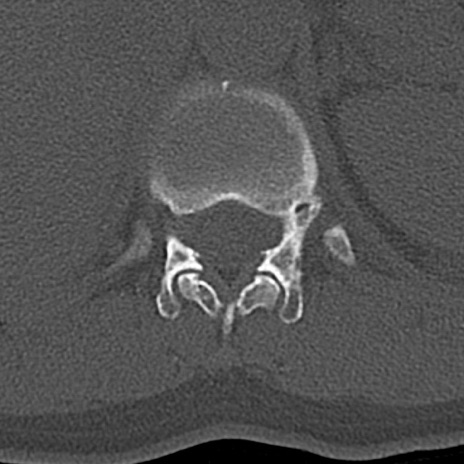

【整形】TIPS症例4 腰椎CT(横断像)

腰椎CT

横断像と矢状断像